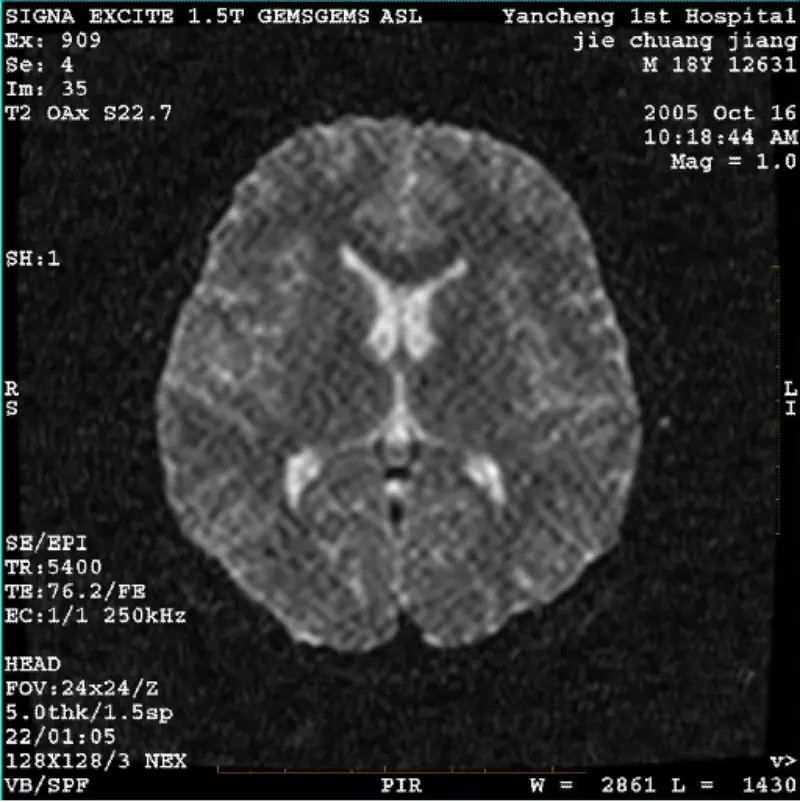

Les merSYSTEM: 1.5T Signa Twin Excite II (programvareversjon 11.0M4) PROBLEM/SYMPTO DWI (zoommodus og helmodus) og fiesta (zoommodus og helmodus) bilde med synlig nett- eller kordfløyelartefakt uansett når du bruker kroppsspole eller hode spole, virker annet rutinebilde normalt